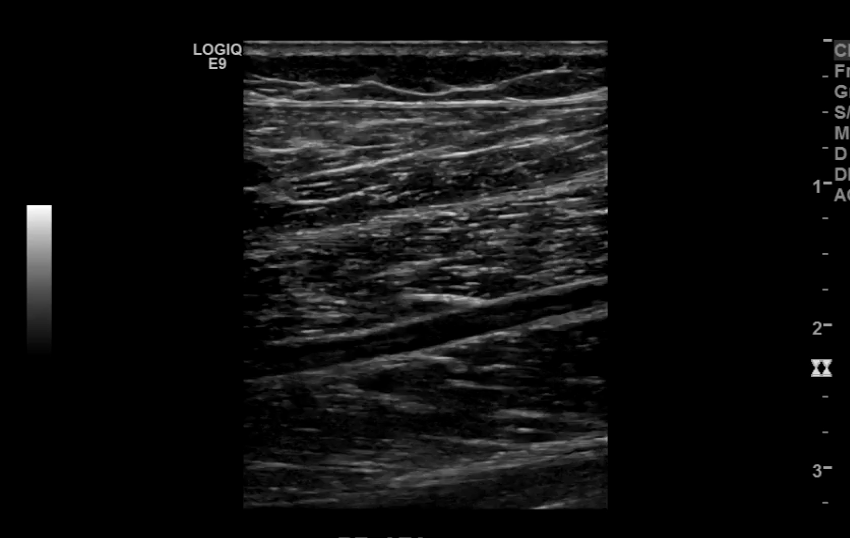

The iliac arteries bifurcate into external and internal iliac arteries (EIA and IIA). The EIA continues caudally turning into the common femoral artery (CFA) which further bifurcates into superficial femoral (SFA) and deep femoral artery (aka profunda femoris). The SFA then converts into the popliteal artery which bifurcates into the tibioperoneal trunk and anterior tibial artery (ATA). The tibioperoneal trunk bifurcates into posterior tibial artery (PTA) and the peroneal artery. The anterior tibial artery descends further to become the dorsalis pedis artery (DPA).

Anterior Tibial Artery